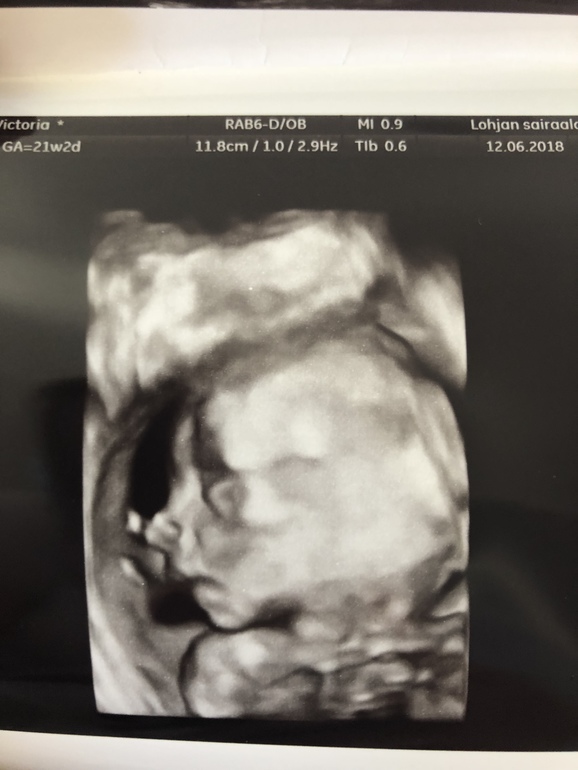

Срок 21+2 все в полном порядке, все соответствует сроку:) вес 396гр. И мальчика нам подтвердили🙈😍💙💙💙 люлька с синим капюшоном уже дома , одежду начала покупать , я в счастливом шоке! Также не может н

радовать что я худею потихоньку , добеременности 95,7 сейчас 90,7:) хочу ещё :) Ну и фоточек несколько , т к плацента по передней стенке Было очень трудно сфотать